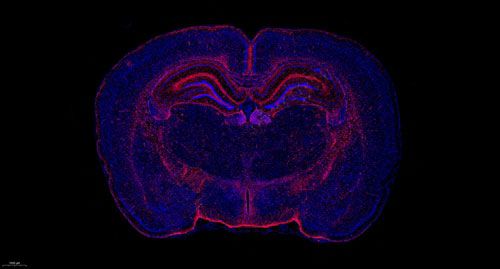

大鼠脑 普通切片扫描(荧光单标 双色)

小鼠心 普通切片扫描(荧光单标 双色)